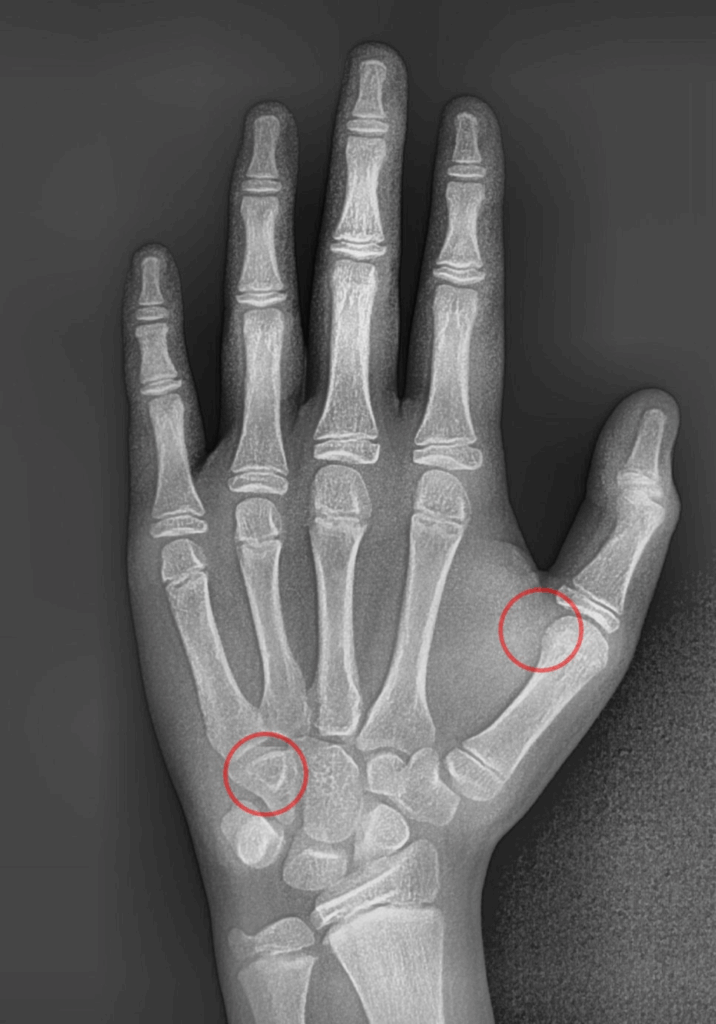

같이 검사할 수 있는 수완부 엑스레이 촬영(성장기 검사)

23.08.17

아이들의 경우 성장기에

치료를 시작하는 것이 효과적입니다.